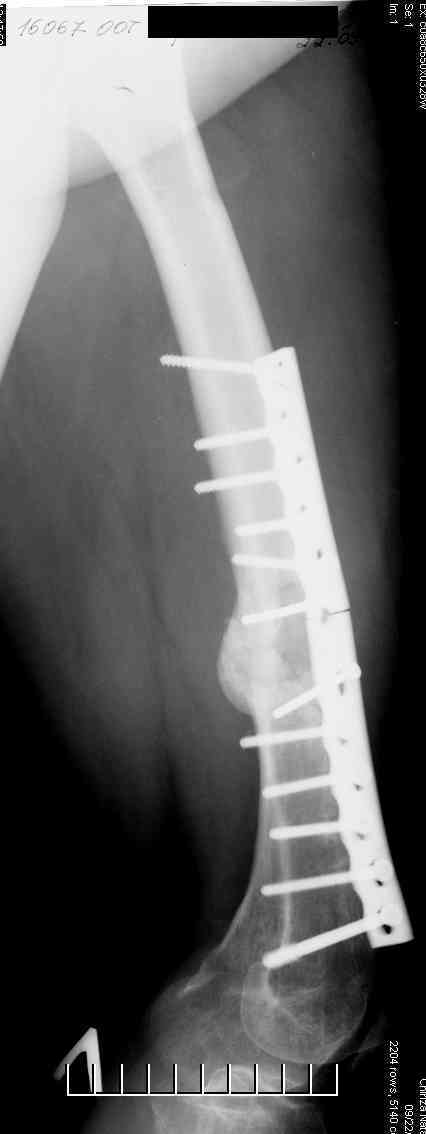

Соматически здорова. В ноябре 2004 года падение с высоты 12 м, перелом правой вертлужной впадины со смещением, неврит седалищного нерва, откр. перелом дистального отдела большеберцовой кости справа и закрытый перелом с/н/3 левого бедра. К нам поступила через 3 недели после травмы, был выполнен в 2 сессии сначала интрамедуллярный ретроградный остеосинтез бедра слева, затем остеосинтез вертлужной впадины и голеностопа справа. При остеосинтезе бедра пришлось немного приоткрыться в зоне перелома для репозиции и вообще операция затянулась часа на 2.5-3 (это один из наших первых интрамедуллярных синтезов). Через 4 месяца при нагрузке весом около 50 кг постепенно развилась варусная деформация бедра с искривлением стержня. Закрыто выпрямили под наркозом, динамизация гвоздя,но в сентябре 2005 г. согнулось бедро снова. Гвоздь удалили, остеосинтез пластиной, декортикация, пластика спонгиозой из метафиза б/берцовой кости. Динамика заживления вялая, но конструкция стояла неплохо (без признаков расшатывания), постепенно дали нагрузку - в марте 2006 года - перелом пластины - реостеосинтез пластиной, пластика гребнем подвздошной кости. На контролях (за август, т.е. 4 мес. после операции - прилагаю) динамика положительная, разрешена нагрузка до 50 кг. В начале этой недели без падения вновь появились боли в бедре - на Р-граммах - перелом пластины (снимки прилагаю). Фоном ко всему этому то, что и перелом вертлужки и дистального отдела б/б кости тоже не срастаются, хотя на голени уже дважды выполнялась костная пластика, на впадине - вторичное смещение, перелом части металлоконструкций. Исследовали гормональный фон - парат-гормон и прочие щитовидные в норме, месячные регулярно.Прошу совета по тактике дальнейшего лечения и выяснения причины тотального несращения всего сломанного.

В приложении рентгенограмма бедра за авгутст 2005 с согнутым гвоздем и первичные.